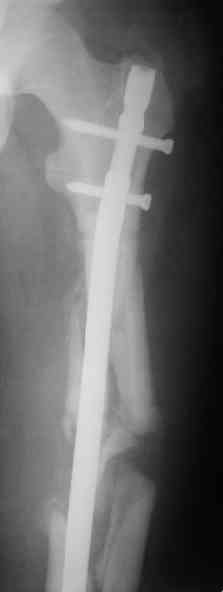

> денамизация - февраль 2006. ( 3 и 4 снимки) на сегодняшний день (снимок 5) беспокоит боли в тбс...

Однозначно: удалить, рассверлить, перештифтовать более толстым гвоздем. ЭТОТ 9 мм будет? Возьмите 12-14.

Дистально обязательно два винта! Проксимально можно один динамический. Больной будет счастлив на следующий же день!

Учитывая точку введения - верхушка б\вертела - что бы исправить варус взял бы соответствующий гвоздь: длинную Гамму или PFN или Recon